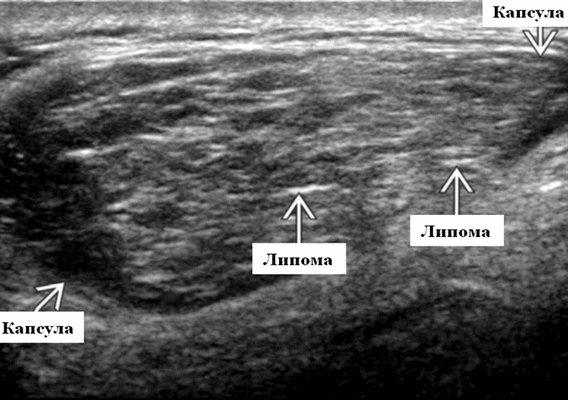

УЗИ липомы околоушной железы

Липома околоушной железы при ультразвуковом исследовании

- На УЗИ слюнных желез четко выраженное, слегка дольчатое поражение.

- Гомогенно гипоэхогенный вид по отношению к паренхиме околоушной железы; гиперэхогенный по сравнению с мышечным слоем

- Линейные гиперэхогенные полосы идут параллельные датчику имея вид «перья в полоску»

- Эхогенные линии внутри поражения остаются параллельными датчику независимо от плоскости сканирования.

- Отсутствие акустического усиления или заднего затенения

- Отсутствие кальцификации, узловатости или некроза.

- Отсутствие значительной васкуляризации в / вокруг массы.

Ультразвуковая визуализация и общие особенности. Лучший диагностический метод - проведение УЗИ слюнных желез. На исследовании определяется хорошо выраженная, гипоэхогенная с линейными гиперэхогенными полосами параллельными датчику опухоль, имеющей перисто-полосатый вид. Плотность жира хорошо определяется на КТ или интенсивность сигнала жира на МРТ

Результаты ультразвукового исследования слюнных желез

Серошкальное УЗИ. Четко выраженное легкое дольчатое поражение. Эллиптической формы с длинной осью, параллельной коже. Сжимаемое образование с помощью ультразвукового датчика. Гомогенно гипоэхогенный вид по отношению к паренхиме околоушной железы и гиперэхогенный по сравнению с мышечным слоем. Эхогенность липом может варьироваться в зависимости от соотношения жира и воды в очаге поражения. Линейные гиперэхогенные полосы, параллельные датчику имеют перисто-полосатый вид, при этом нет заднего акустического усиления или затенения. Образования без кальцификации, узловатости или некроза

Цветной допплер. Нет значительной васкуляризации в / вокруг опухоли